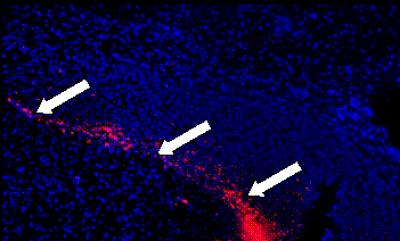

Glioblastoma is the most common ma-lignant primary brain tumor in adults. The aggressive growth manner, characterized by marked angiogenesis and extensive tumor cell invasion into normal brain parenchyma with frequent formation of tumor microsatellites at distal sites, makes eradication impossible even after extensive microsurgical resection combined with current standard chemoradiation and adjuvant temozolomide. Thus, novel therapeutic strategies must to be investigated for the development of a more effective treatment strategy. Stem cell-based therapies are emerging as novel cell-based delivery vehicle for therapeutic agents. Prof. Qingjun Zhang and team from the Department of Neurosurgery, Peking University People's Hospital proposed that umbilical cord mesenchymal stem cells may have similar targeting capabilities for glioma. The researchers found that human umbilical cord mesenchymal stem cells demonstrated excellent glioma-specific targeting capacity in established rat glioma models after intratumoral injection or contralateral ventricular administration in vivo. These findings were published in the Neural Regeneration Research (Vol. 8, No. 22, 2013).

Article: " Migration capacity of human umbilical cord mesenchymal stem cells towards glioma in vivo " by Cungang Fan, Dongliang Wang, Qingjun Zhang, Jingru Zhou (Department of Neurosurgery, Peking University People's Hospital, Beijing 100044, China)

Fan CG, Wang DL, Zhang QJ, Zhou JR. Migration capacity of human umbilical cord mesenchymal stem cells towards glioma in vivo. Neural Regen Res . 2013;8(22):2093-2102.